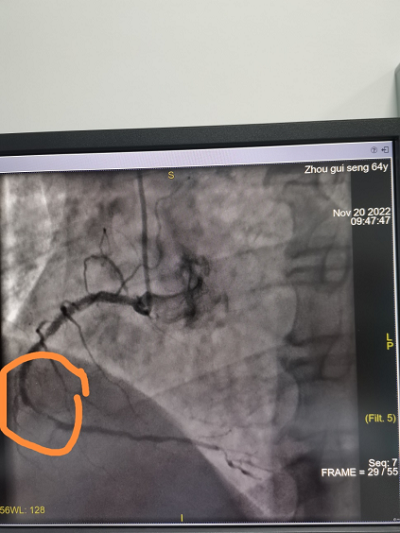

义诊高峰期,急诊科来了位急性下壁心肌梗塞的患者,涂小明主任立即安排好部分人员继续义诊,同时带领介入室团队回医院开展急诊手术,经过一个小时的抢救,成功地为病人开通了堵塞的血管 ,让心脏重获血液供应。

心脏介入导管室配备美国GE数字减影血管造影机(DSA),主动脉球囊反搏系统及临时起搏器,能24小时全天候开展冠脉介入诊疗、心律失常射频消融、单双腔心脏起搏、外周血管造影及支架植入等一系列高难度三四级手术。